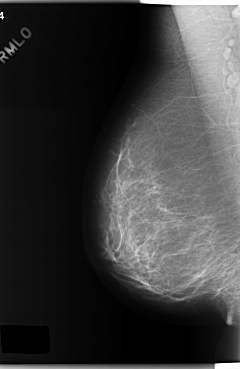

C_0187_1.RIGHT_MLO

RIGHT_MLO LINES 5904 PIXELS_PER_LINE 3832 BITS_PER_PIXEL 12 RESOLUTION 50 NON_OVERLAY